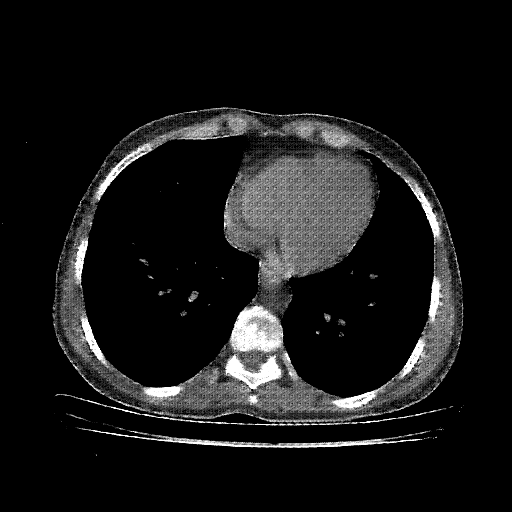

Original VENOUS CT scan

Full window (WL 1023.5, WW 4095 β†’ Low βˆ’1024, High +3071)

Lung window (WL -600, WW 1500 β†’ Low βˆ’1350, High +150)

Mediastinum window (WL 40, WW 400 β†’ Low βˆ’160, High +240)